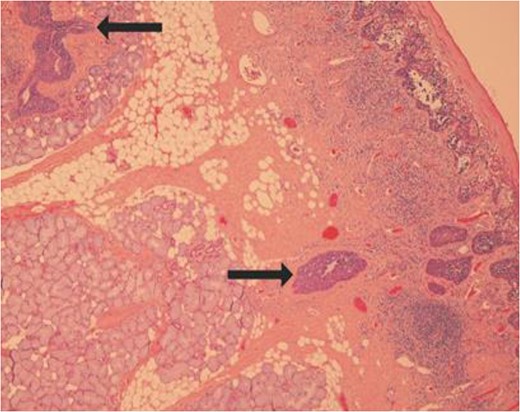

The patient was treated with wide local excision of the mucosa of the hard palate, labial maxillary gingivae and bilateral buccal mucosae. Histopathological analysis of the specimen revealed involvement of all margins with EMPD (Fig. 2).

Slide showing ductal colonization by the tumour cells as shown by the arrows.